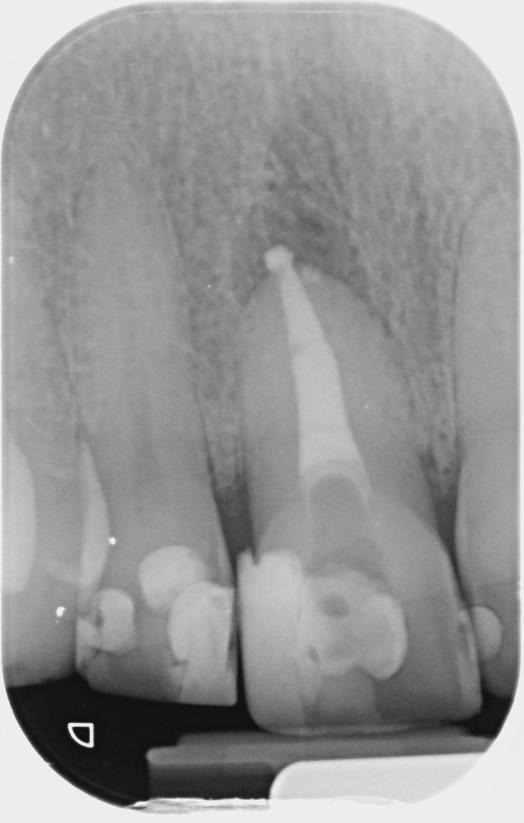

Post-op IOPA’s

Overall, a good result with both teeth and a nice lateral fill on the UL2. A 1-year CBCT review is planned to assess the healing of this case which the patient was fully on board with. I’ll add this in once I have it.